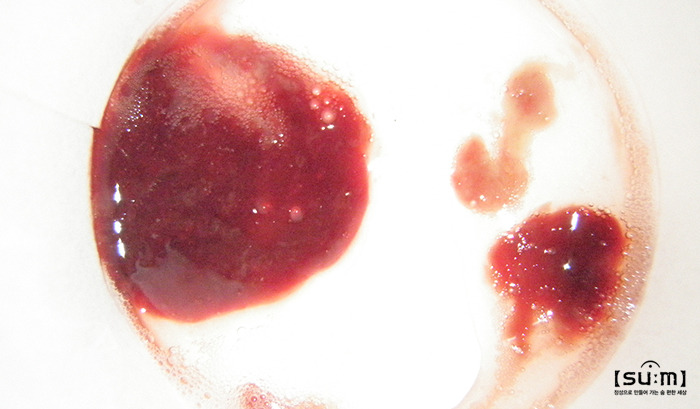

갈색·빨간색·검붉은 가래

분홍빛이나 붉은색을 나타내는 가래는 호흡기가 자극되어 출혈이 있었다는 뜻이다. 출혈이 의심될 때는 즉시 전문의와의 상담을 통해 정확한 진단을 받는 것이 중요하다. 검붉은 가래는 대부분 먼지, 대기오염, 담배 연기 등이 원인이다. 이 외에도 폐곰팡이 감염을 예로 들 수 있다. 담배를 오래 피운 사람은 폐 밑 깊숙한 곳에 가래가 남아 있기 때문에 '그르렁' 소리가 난다.

가래에 피가 섞여 나오는 것은 '객혈' 증상이라고 한다. 원인은 매우 다양하다. 일시적인 객혈은 '기관지 염증', '후두염'에 의해 발생할 수 있지만 재발되거나 지속되는 객혈은 '폐렴', '결핵', '폐암', '기관지 확장증' 등에 의해 나타나기 때문에 객혈 증상이 나타날 때는 즉시 병원에서 진단을 받아보길 바란다.

581292.jpg